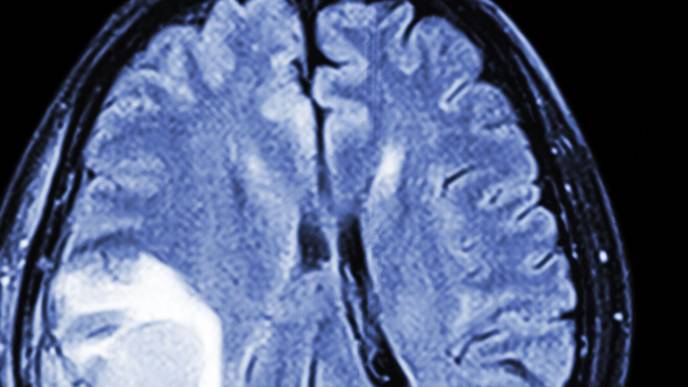

image: A schematic illustration of size-tunable PEG-grafted copolymers (gPEGs) for optimizing the passive glioblastoma multiforme (GBM)

targeting. MW, molecular weight; BBTB, blood−brain tumor barrier; i.v., intravenous; RES, reticuloendothelial system.

Innovation Center of NanoMedicine (iCONM; Center Director: Kazunori Kataoka; Location: Kawasaki, Japan) has announced with the Graduate School of Engineering of The University of Tokyo that a group led by Prof. Kanjiro Miyata, Visiting Scientist of iCONM (Professor, Department of Materials Engineering, The University of Tokyo), has found that the threshold for tissue permeability of brain tumors was in the range of 10−30 nm, using “Nanoruler” (Note 1) which is a biocompatible polymer used for measurement of “gaps in the body”. Especially, by adjusting the size of the nanoruler to 10 nm, it achieves an unprecedentedly high brain tumor accumulation. Obtained results have provided significant guidance for the design of future brain tumor nanomedicine.

Currently, there is no effective treatment for glioblastoma multiforme (GBM), the most frequent and malignant type of brain tumors. Some low molecular weight antitumor agents are used to permeate the gaps between endothelial cells in the BBTB (Blood−Brain Tumor Barrier), which is a characteristic blood vessel structure and formed by the partial collapse of the blood−brain barrier, but they are rapidly excreted from the kidneys, resulting in low GBM accumulation. Besides, their nonspecific distribution in healthy tissues often induces severe side effects such as myelosuppression and immunosuppression. It is known that 30−100 nm-sized nanomedicines avoid rapid renal excretion and increase drug accumulation efficiency in some tumor models. However, the GBM accumulation level of such nanomedicines remains limited, presumably because of the relatively low blood vessel permeability in the BBTB. Thus, Miyata et al. studied about size-dependent GBM targetability using a size-tunable stealth polymer, termed “polymeric nanoruler”, and reported the results in an international journal “Bioconjugate Chemistry” (Note 2) as follows:

In conclusion, this study explored the size effect of nanomedicine on passive GBM targeting with size-tunable poly(ethylene glycol)-grafted copolymers (gPEGs) as polymeric nanorulers (ranging from 8.5 to 30 nm). Small gPEGs exhibited efficient brain tumor accumulation, with 10 nm of gPEGs achieving the highest accumulation level (19 times higher than that in the normal brain region and 4.2 times higher than that of 30 nm of gPEGs), presumably because of the optimal size associated with enhanced BBTB permeability and prolonged blood circulation.